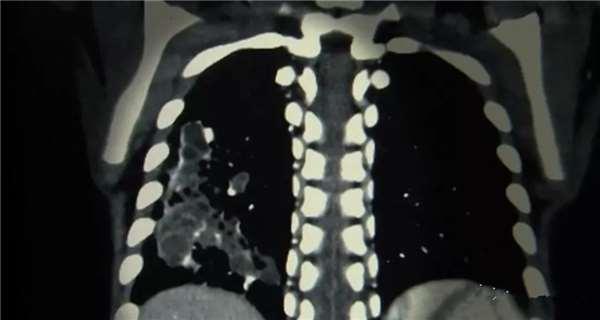

這位名叫桐山波琦的小女孩,之前斷斷續續肺炎發作過好多次,原來,她的肺部生長了多處囊腫,因為這些囊腫,去年一場肺炎,差點要了她的命,因此,切除這些病變的部位刻不容緩。

這個手術需要切除波琦的右肺下葉(深色部分)。

但這附近有肺動脈和肺靜脈經過,手術中,必須先止住動脈和靜脈的血流(結紮),然後才能順利切走病變的部分。